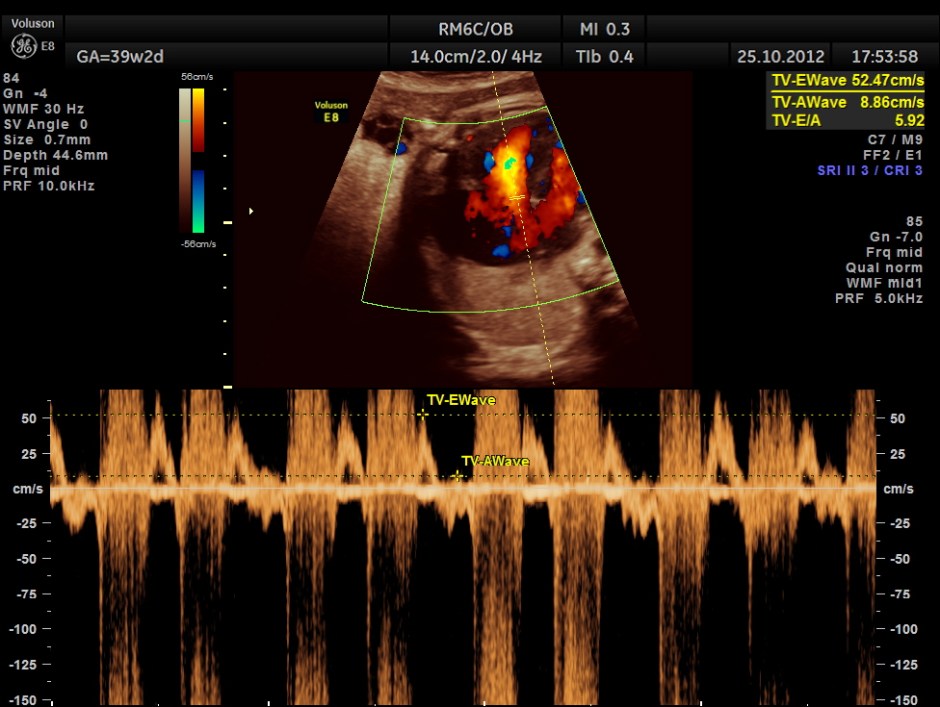

THIS FETUS HAD SEVERE FETAL ANEMIA WITH CARDIAC FAILURE LEADING TO CARDIOMEGALY WITH MITRAL, TRICUSPID AND PULMONARY REGURGITATION .NO OTHER OBVIOUS CARDIAC ANOMALY WAS MADE OUT . THE VENO ATRIAL , ATRIO VENTRICULAR AND VENTRICULO ARTERIAL CONCORDANCE APPEARED TO BE NORMAL; NO SEPTAL DEFECT WAS MADE OUT.